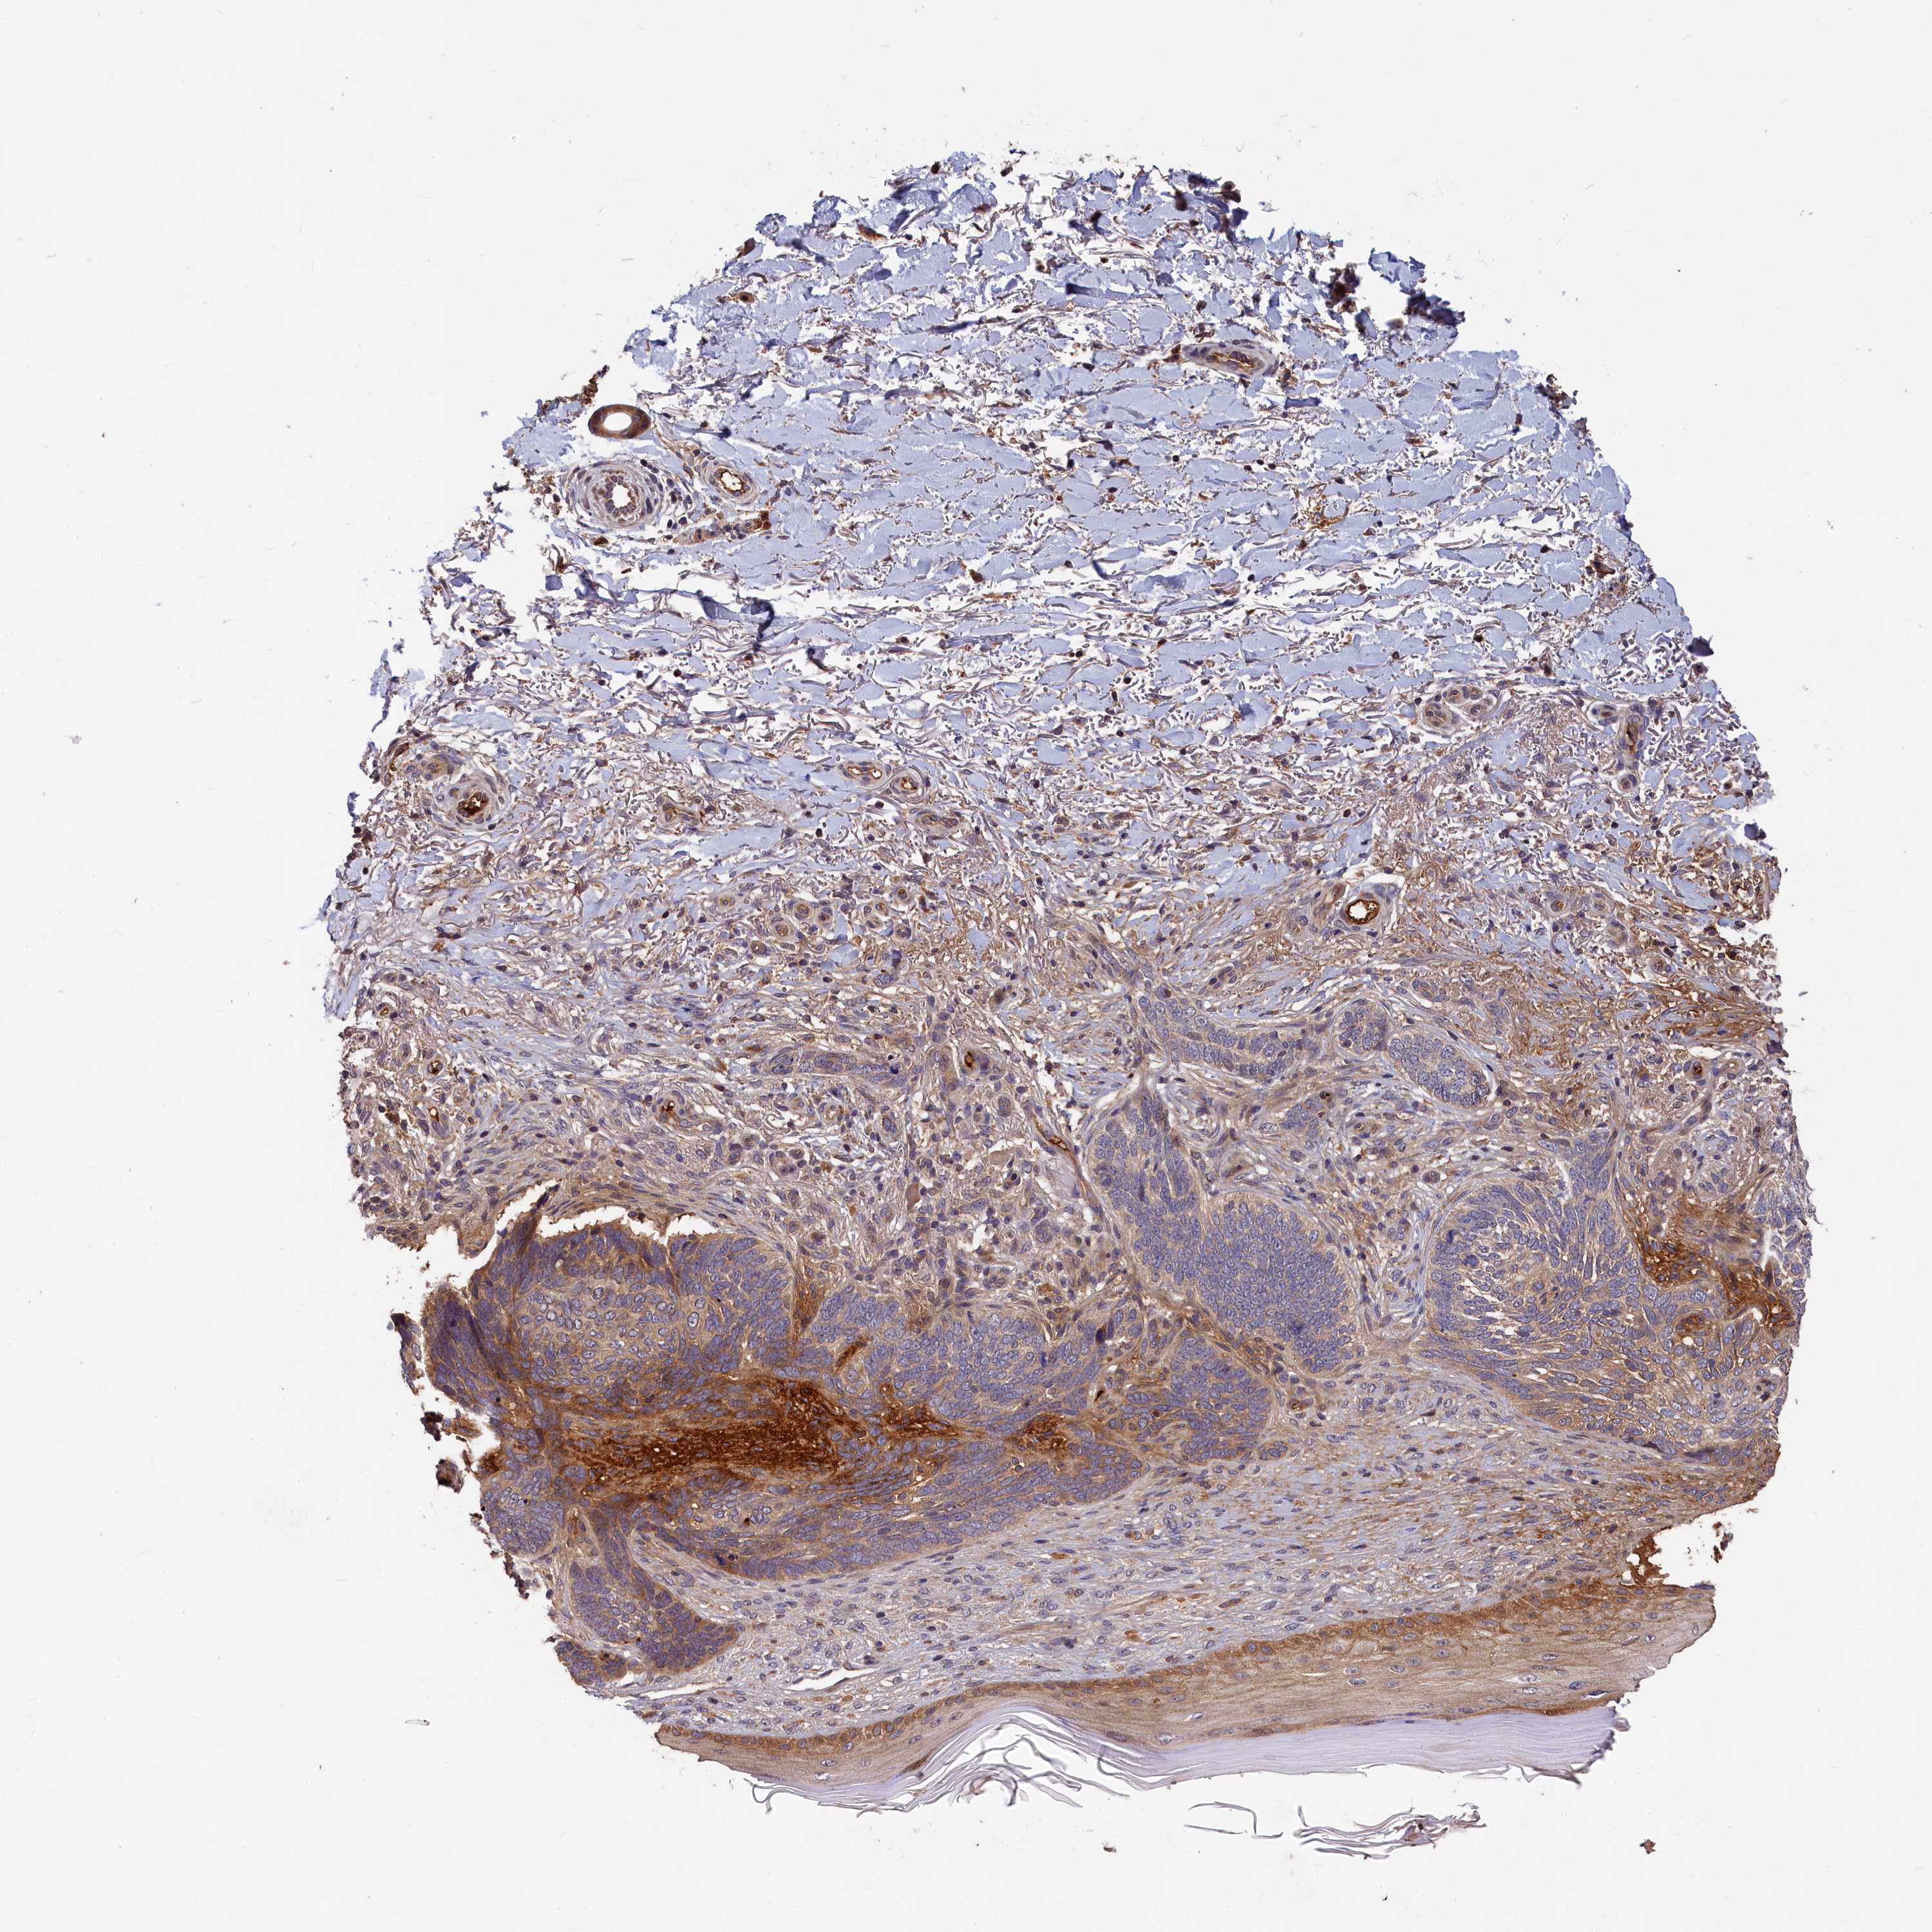

Basal cell and squamous cell cancer

SKIN CANCER - Protein expressioni

A mouse-over function shows sample information and annotation data. Click on an image to view it in a full screen mode. Samples can be filtered based on level of antibody staining by selecting one or several of the following categories: high, medium, low and not detected. The assay and annotation is described here.

Each image is clickable and will lead to virtual microscopy that enables deeper exploration of all samples and also displays staining intensity scores, fraction scores and subcellular localization as well as patient and tissue information for each sample.

Antibody HPA042049

Squamous cell carcinoma, NOS

Squamous cell carcinoma, metastatic, NOS